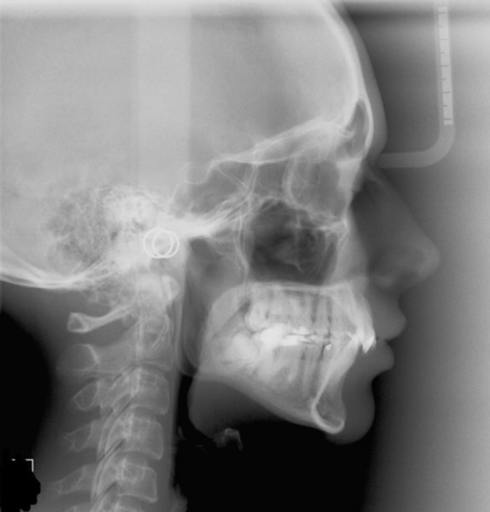

Do I require lefort 1 advancement?

I am 9 months post sarpe. My orthodontist said I should ask my surgeon if I should do lefort 1. My surgeon says I wouldn’t need lefort 1 advancement unless my ortho tilts my bottom front teeth out. What should I do and what questions and procedures...

Overjet? Braces? Is my upper jaw forward or my lower jaw back??

I am 26 yr old female and i have finally gathered the money to get my braces done. Over the years i have been told that my lower jaw is "pushed back" and it could cause problems when am older. The last orthodontist i went to, mentioned that i have...